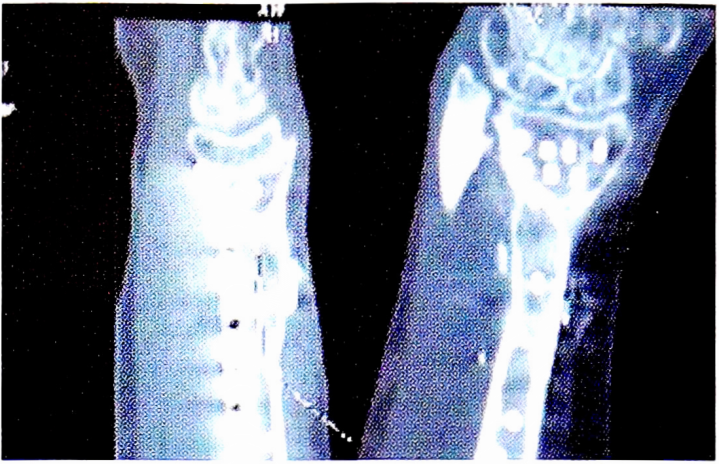

Клинический пример 7. Пациент Г. в результате огнестрельного ранения дробью получил открытый огнестрельный перелом нижней трети правой лучевой кости. В день травмы прооперирован: выполнены остеосинтез аппаратом наружной фиксации и первичная хирургическая обработка ран. В ходе наблюдения в течение 9 мес выявлены признаки формирования ложного сустава лучевой кости. С учетом малого размера дефекта и нарушенного кровообращения в данной области было принято решение резекции зоны ложного сустава с замещением дефекта васкуляризованным трансплантатом из медиального мыщелка бедренной кости. Результат, полученный через 14 мес, представлен на рис. 2.

Рис. 2. Данные KT предплечья через 14 мес после пластики внутренним мыщелком БК. КТ — компьютерная томография; БК — бедренная кость.

Fig. 2. СТ data of the forearm 14 months after plastic surgery by the inner condyle of BC. CT — computed tomography; BC — femur.